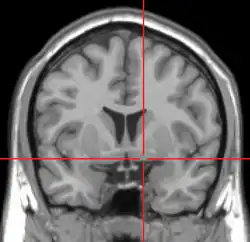

Repérage de la substance innominée de Reichert par IRM.